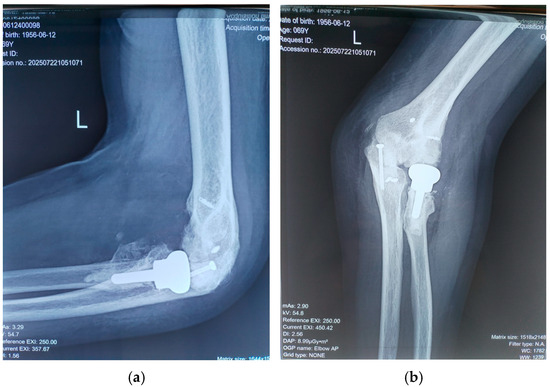

Sutures were removed at two weeks postoperatively. Follow-up assessments occurred at six weeks, three months, and 18 months, at which point the patient’s MEPI score had improved to 95 (Table 2). Between four and six weeks post-surgery, passive exercises were gradually replaced by active movements. No wound infections or ulnar nerve deficits were observed. Follow-up radiographs at 18 months confirmed maintained reduction, proper positioning of the radial head prosthesis, and no recurrence of heterotopic ossification (Figure 5).

Figure 5.

(a) Lateral and (b) anterior view of elbow at 18 months after surgery.